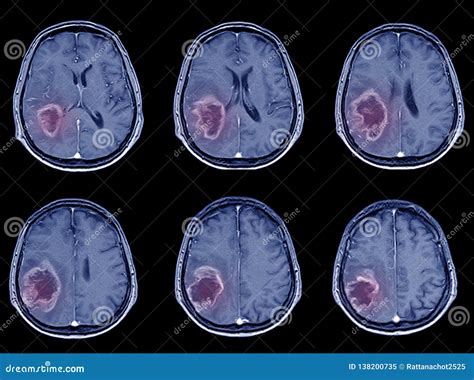

Interpreting Ischemic Stroke CT Results

Interpreting the results of an Ischemic Stroke CT scan requires expertise and experience. Radiologists and neurologists work together to analyze the images and make a diagnosis. Key findings that may be observed include:

• Early ischemic changes: These can appear as areas of low density (hypodensity) in the brain tissue, indicating reduced blood flow.

• Hyperdense artery sign: This is a bright appearance of an artery on a non-contrast CT scan, suggesting the presence of a blood clot.

• Mass effect: Swelling or compression of brain tissue due to the stroke, which can be seen as a shift in the midline structures of the brain.

These findings help healthcare professionals determine the type and severity of the stroke, as well as the appropriate treatment plan.